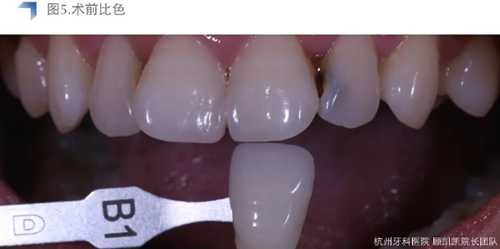

待貼面制作修整完成后,用DMG Vitique Tr.色配套試色糊劑口內(nèi)試色。

小結(jié):Vitique Tr.在本病例中試色與術后粘接未見明顯差異,能恰當表現(xiàn)e.max B1 mt的通透度和明度,美學效果優(yōu)異??紤]到患牙較近髓,長期隨訪和術后常規(guī)勿咬硬物及冷熱刺激,十分必要。